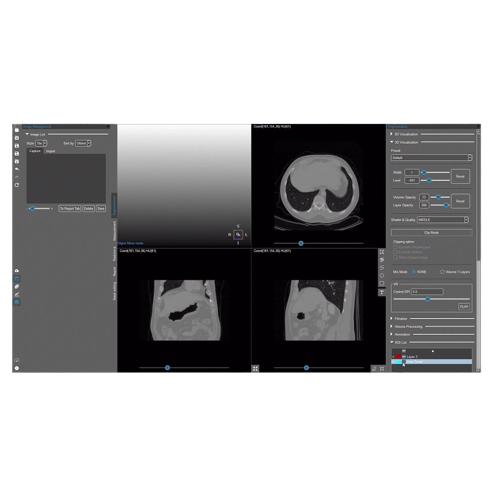

MEDICAL IP MEDIP PRO

- Brand :

- MEDIP PRO

- MOQ :

- 1 ea

USD 35,000.00 -

MEDICAL IP, MEDICAL IP MEDIP PRO, AI Software,Digital Twin,AI Segmentation, AI Software,Digital Twin,AI Segmentation

- Brand :

- MEDIP PRO

- Size :

- AI Solution

- MOQ :

- 1 ea

USD 35,000.00MEDICAL IP- Business Type

- Manufacturer

- Main Product

- MEDIP PRO, DeepCatch, TiSepX, MDBOX, ANATDEL